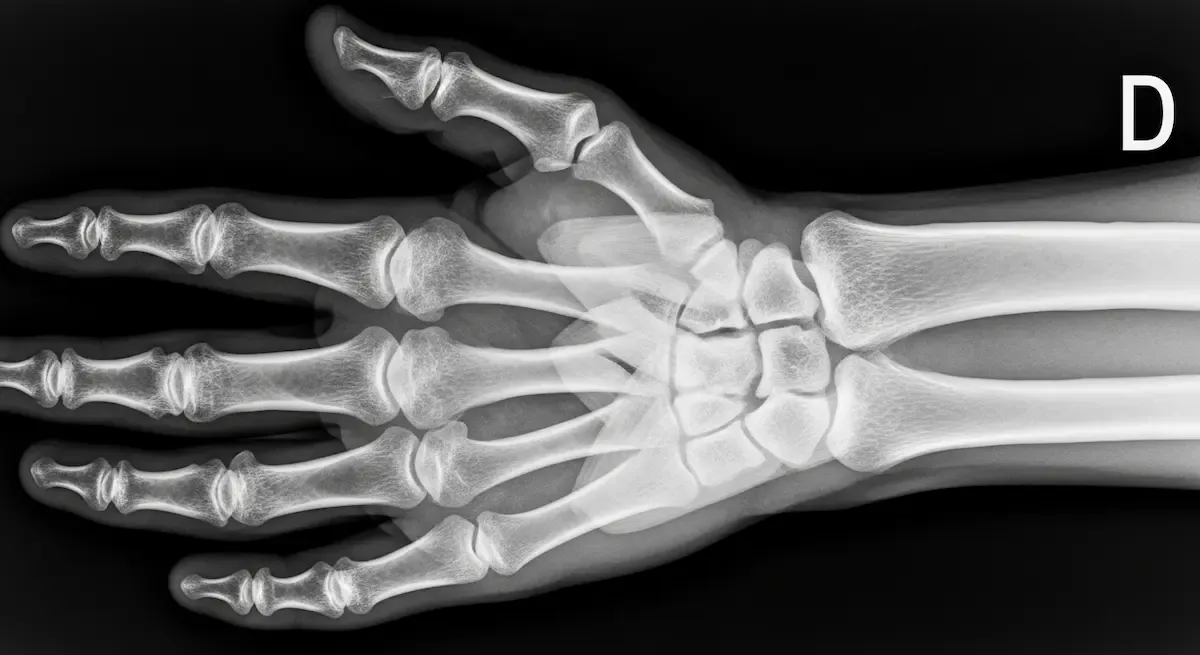

Macrodactilia: Sinais, Diagnóstico e Tratamento

Ao longo de anos dedicados à cirurgia da mão, poucos desafios se comparam à complexidade do tratamento da macrodactilia. Esta condição rara, caracterizada pelo crescimento anormal e desproporcional de um ou mais dedos, afeta aproximadamente 1 em...